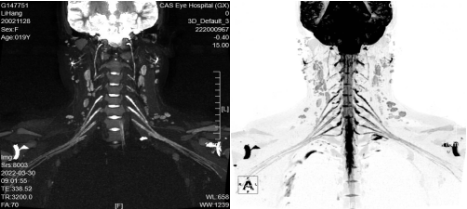

二、臂丛神经MRI成像(腰骶丛神经MRI成像)

上图是放射科开展的“臂丛神经MRI成像(腰骶丛神经MRI成像)”新业务ai辅助诊断收费,臂丛(腰骶丛)像一个复杂的地铁交通网,支配着上肢的感觉与运动。全球医学治疗难题之一就是臂丛神经损伤,它会导致患者上肢运动功能感觉的部分丧失或完全丧失,影响了患者的日常生活与工作。熟练掌握其分支、走形分布等可以为手术成功、减少术后并发症提供最有力的保障。当前对于臂丛及腰骶丛神经病变的诊断主要依靠临床症状、体征及电生理学检查等方法,但不能直观、准确观察神经损伤后形态学变化及周围结构的空间信息,对手术方案的选择及病情预后判断较为困难。MRI可以清晰显示臂丛及腰骶丛神经全貌及周围结构关系,为臂丛及腰骶丛神经创伤或肿瘤患者术前诊断及术后长期随访提供重要的信息,其在臂丛及腰骶丛神经诊断中有不可替代的作用。

MRI有以下优点:

(一)使正常神经显示为稍高信号,能清晰辨认神经内神经纤维束等结构;

(二)准确判断神经损伤部位和程度;

(三)准确评估病变是位于神经内还是神经外,这对判断肿瘤是否浸润脊髓以及选择治疗方案有重要意义。

适应症:外伤、肿瘤、炎症等疾病怀疑臂丛(腰骶)神经病变。

意义:能全程清晰显示臂丛(腰骶)神经,达到定性、定位的诊断ai辅助诊断收费,为精准治疗提供支持。

注意事项:需注入造影剂“钆喷酸葡胺”增强扫描。